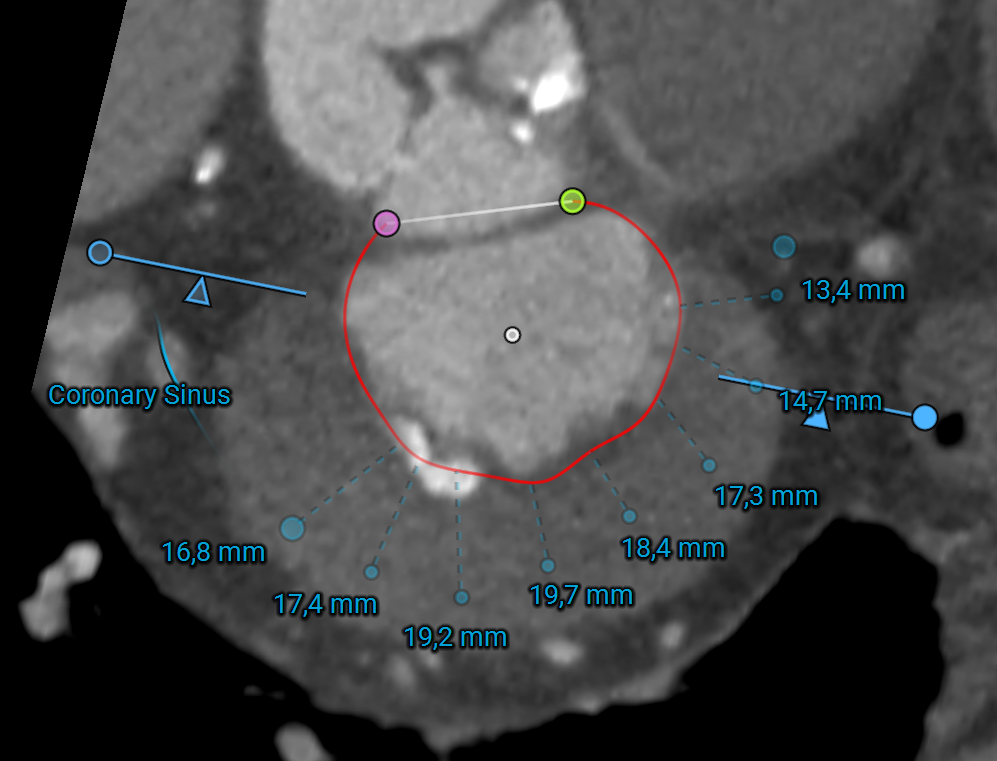

• Carillon Mitral Contour System (Cardiac Dimensions): Indirect annuloplasty device deployed in the coronary sinus to reduce annular dilation and improve mitral leaflet coaptation.

coronary_sinus.png

1. Cardiac CT plays a central role by providing detailed measurements of the mitral annulus, assessing the predicted neo-LVOT area to avoid left ventricular outflow tract obstruction, and identifying calcium distribution across the annulus and leaflets.

Planning software like 3mensio Structural Heart can can streamline TMVR planning by providing accurate annular sizing, neo-LVOT area prediction, assessment of annular and sub-annular calcification, and simulation of both transapical and transseptal access paths. This comprehensive imaging and planning workflow enables device selection, positioning, and risk management, particularly in anatomically challenging cases.